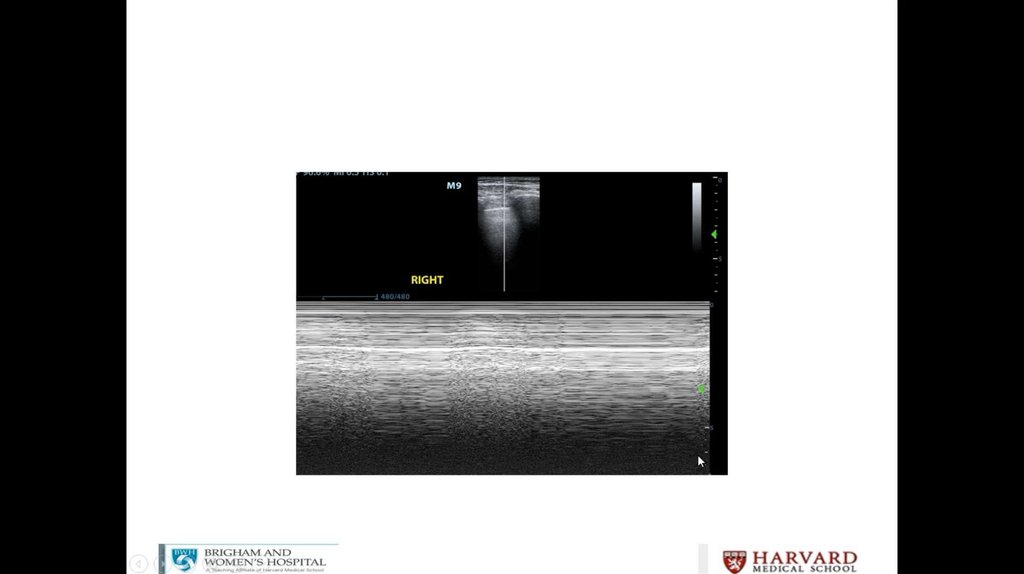

Litrasound in the ICU: What Every Intensivist Should Know